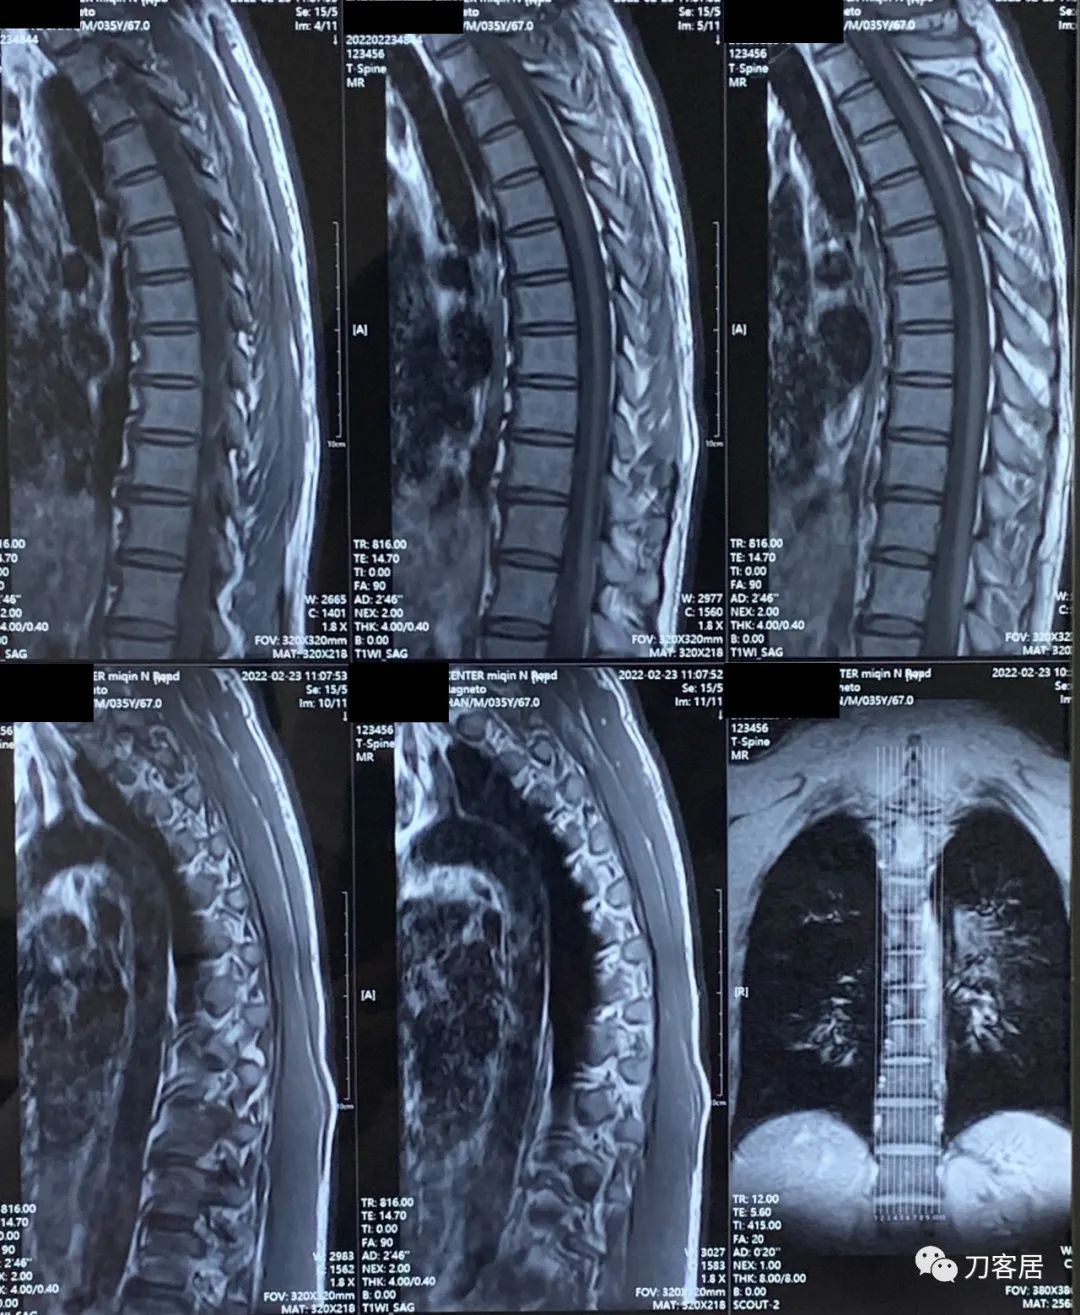

颈椎及胸椎MRI检查后,并没有发现颈椎管及胸椎管有椎间盘突出,也没有椎管狭窄及脊髓受压。

图6. 20220223胸椎MRI01

图7. 20220223胸椎MRI02